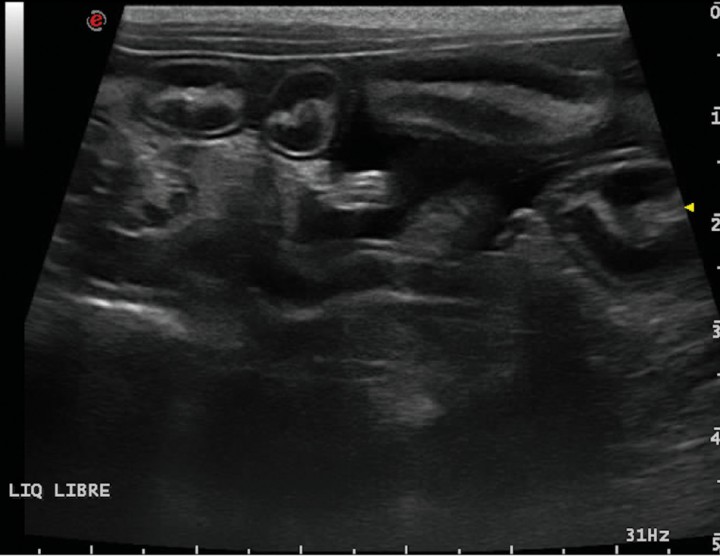

La ecografía hepática mostro un hígado de pequeño tamaño, con presencia de focos hiperecoicos y con sombra acústica (Fig. 2). Los conductos biliares mostraban distensión severa y aspecto tortuoso, manteniendo su comunicación con la vesícula biliar, sin evidencia de obstrucción en algún punto concreto de su recorrido (Fig. 3). La papila duodenal se visualizaba normal. La vena porta presentaba pequeño tamaño, flujo hepatópeto y velocidad aparentemente reducida (Fig. 4). Se evidenció la presencia de múltiples vasos de aspecto tortuoso adyacentes al riñón izquierdo (Fig. 5). Ambos riñones presentan múltiples infartos renales y focos mineralizados en la corteza, sedimento con sombra acústica en pelvis renal izquierda y presencia de cálculos en riñón derecho (Fig. 6). Pequeña cantidad de líquido libre anecoico (Fig. 7).

<p>Corte longitudinal. Líquido libre abdominal anecoico entre asas de intestino delgado.</p>

Figura 7

Corte longitudinal. Líquido libre abdominal anecoico entre asas de intestino delgado.

En nuestro paciente (Figs. 4, 5 y 7) la presencia de estos shunts múltiples, junto con el perfil de flujo portal y la presencia de ascitis, son altamente sugerentes de que el proceso de base está provocando HTP.